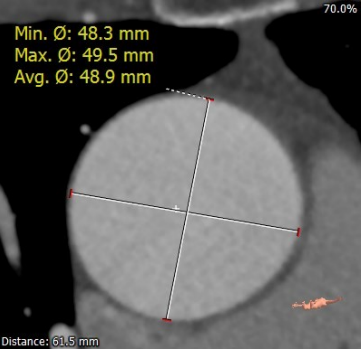

术前陈晓敏教授带领团队对这位患者进行了详细的分析,从CT分析结果显示,患者主动脉瓣为type 0型二叶瓣,瓣环直径为24.4mm,结合患者瓣叶钙化等情况,符合美敦力Evolut PRO 29mm瓣膜选型。经讨论决定以右侧股动脉为主入路,左侧股动脉为辅入路,术中进行23mm球囊预扩张,保证系统顺利跨瓣及释放,并采用世界先进的Cusp Overlap技术植入瓣膜 ,以更精准地释放瓣膜深,减少对患者传导系统的影响。